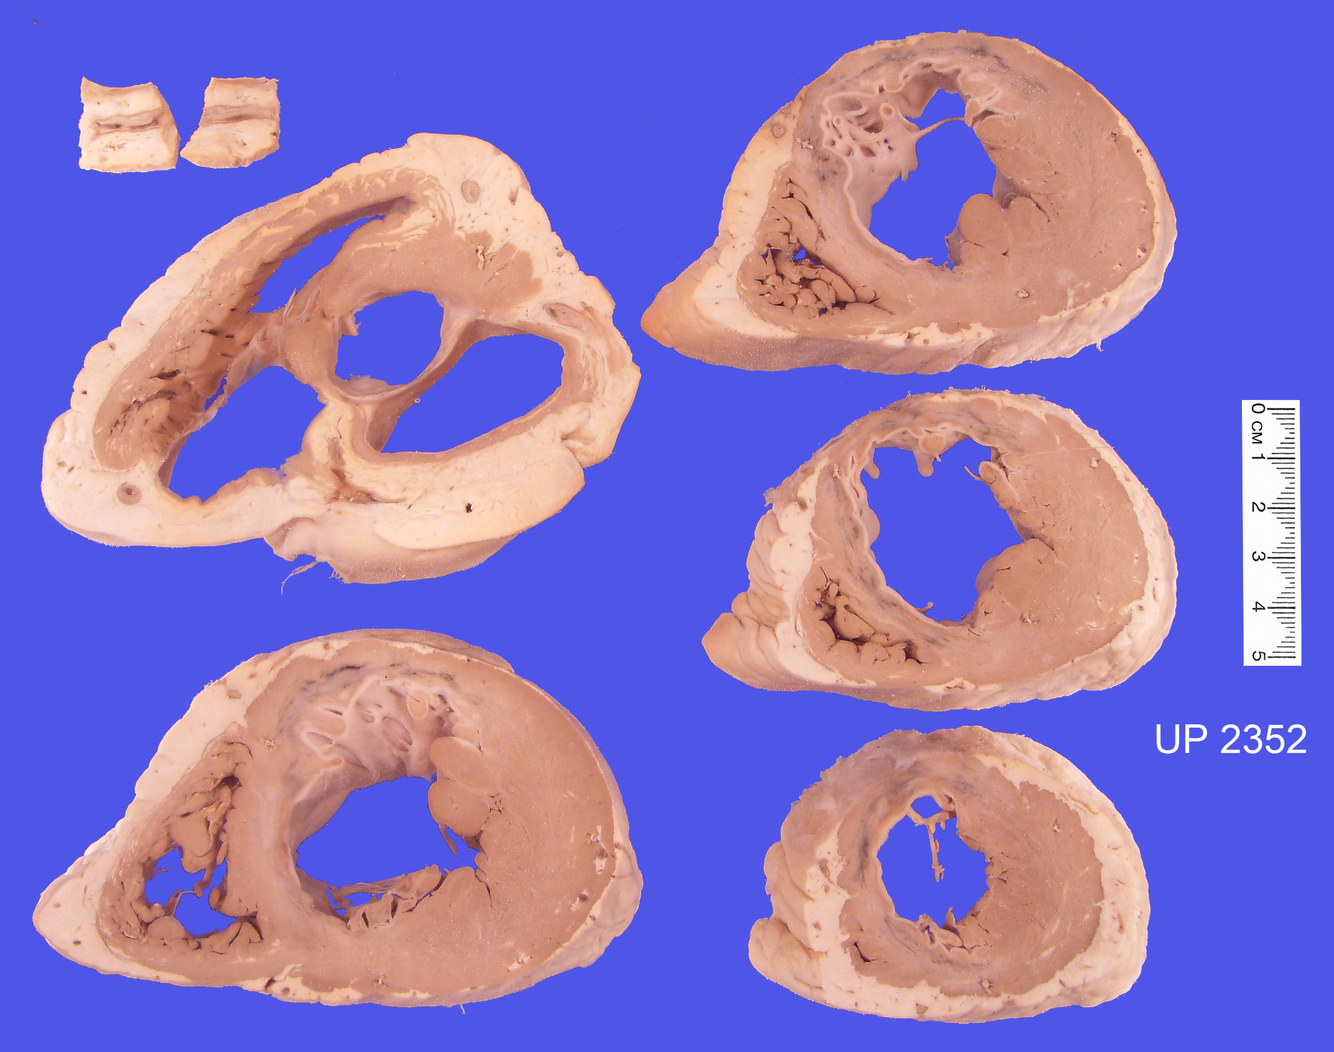

The mounted specimen consists of a series of cardiac slices that show an extensive old anteroseptal infarct. In the area of the old infarct the muscle wall is slightly thinner and contains grey-white scar tissue and there is focal congestion related to the old scar suggestive of a more recent insult. There is also moderate hypertrophy of the uninvolved left ventricular muscle.

Examination of the anterior descending branch of the left coronary shows marked atherosclerotic stenosis but no thrombosis.

All vessels show some degree of atherosclerotic narrowing which, even for the right coronary artery, approaches 50% (see upper left slice).

The forensic postmortem revealed an extensive old antero-septal myocardial infarct and the complete occlusion of the anterior descending branch of the left coronary artery. The old infarct shows relative thinning of the ventricle wall, with grey-white scar tissue and some vascular congestion.

The vessels displayed in the upper corner show a recent thrombus and also a yellow atherosclerotic plaque in a smaller branch vessel.

Although no histological evidence of an acute infarct was found the recent thrombus in the coronary artery would suggest an acute infarct was the most likely reason for the accident. The changes of infarction take time to evolve and this man died before this process could occur. His mode of death would most likely have been a cardiac arrythmia precipitated by the myocardial ischaemia.

The left ventricular wall is markedly hypertrophied suggesting an underlying hypertensive condition.